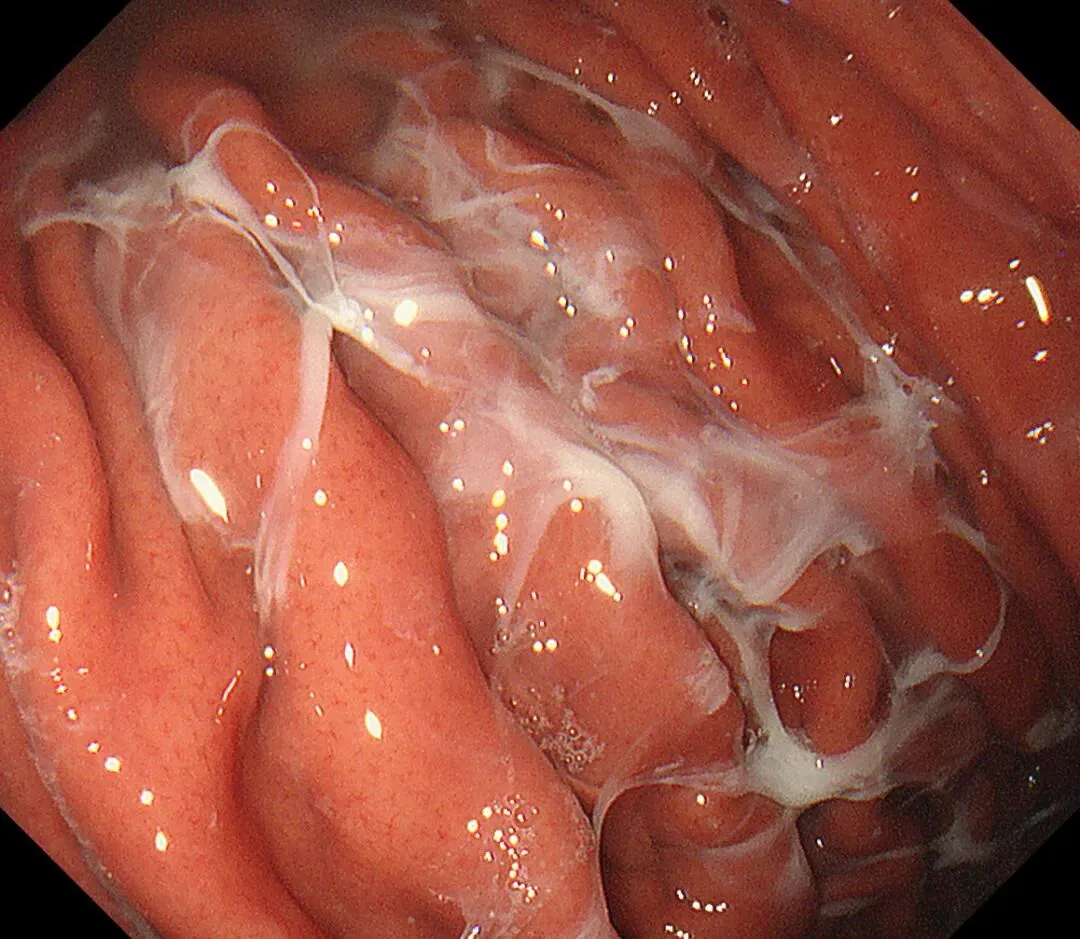

蛛网状黏液case2,服用P-CAB药物)👇

(报道称黏膜斑状或线状发红也是P-CAB药物所致,原因不明